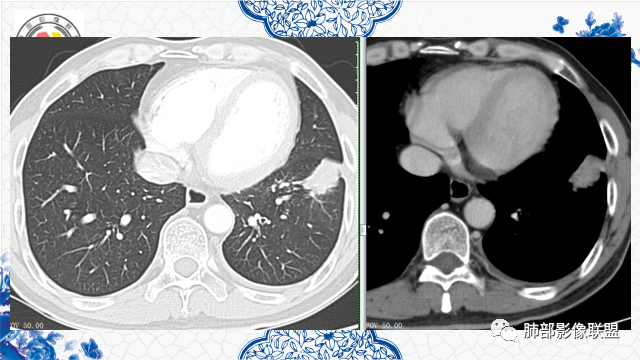

发現肺占位3月,患者既往有肾、胃恶性肿瘤病史。胸部CT:左肺前外基底段近胸膜下不规则实性病灶,分叶,部分边缘平直、部分明显膨隆,内部密度不均匀,周围见磨玻璃影、边界清楚,支气管进入病灶堵塞,血管聚集,胸膜糊墙,增强扫描不均匀强化,内部多发低密度区。综合考虑恶性,转移?鉴别隐球菌、结核。

3月前左肺中下野可见结节灶,现CT可见沿支气管走形融合成团片灶,近端支气管进入后截断,病灶整体以平直收缩为主,局部膨隆,与胸膜呈糊墙样改变,病灶周边可见结节,总体分析病灶是结节融合形成,远端大近端小,符合支气管爬行征,强化后其内可见多发低强化区,低强化边界不清,其内未见血管,首先考虑炎性病灶结核,隐球菌分布不符合,但是也可以有,另外恶性不能排除,建议排查结核、隐球菌,如不能明确,穿刺活检是必要的!

良性的依据有五点::第一,周围收缩,凹陷,桃尖,边缘大部分平直,周围卫星灶。第二,栽脏不明确,第三,强化有环形强化的感觉。第四,有支气管爬行的味道。第五,专门提出三个月前胸片多发小结节,三个月后变大成肿块。

第一,周围收缩,凹陷,桃尖,边缘大部分平直,周围卫星灶。

第二,栽脏不明确,

第三,强化有环形强化的感觉,坏死区太圆太规整。

第四,有支气管爬行的感觉。

第五,专门提出三个月前胸片多发小结节,三个月后变大成肿块。